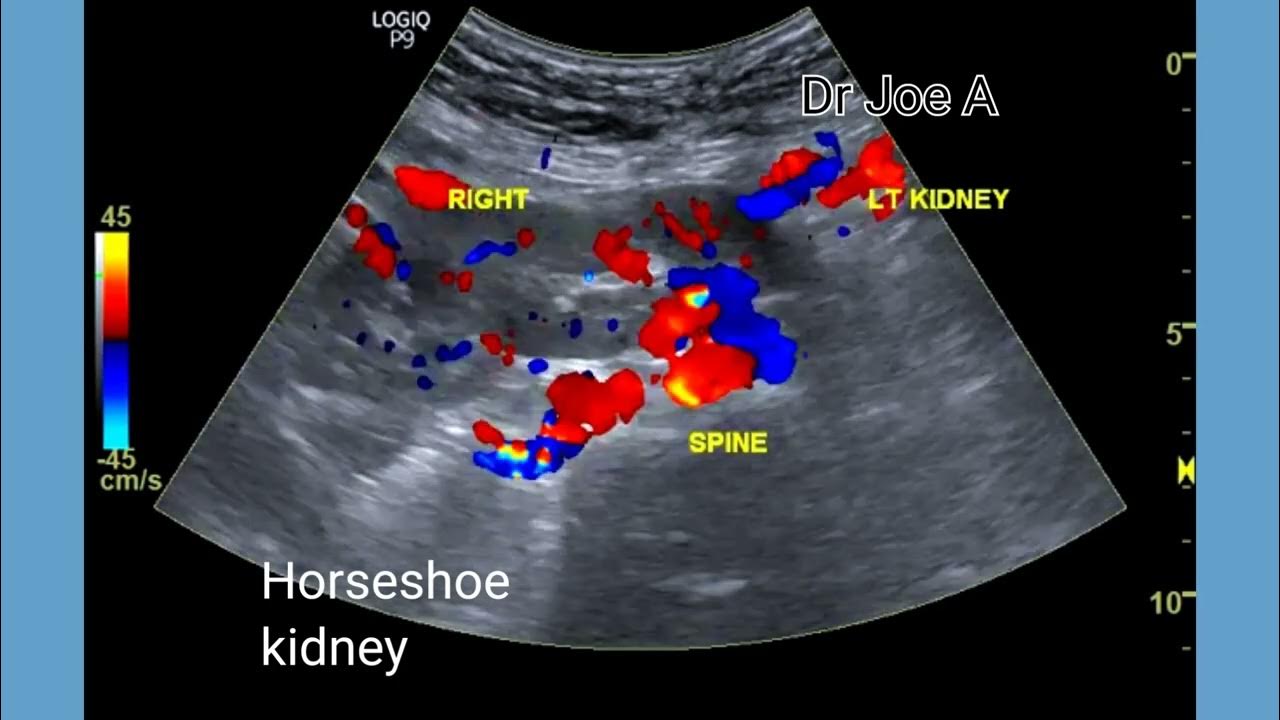

Horseshoe kidney or partial fusion of kidneys ultrasound and color Doppler video YouTube Horseshoe Kidney Treatment Plan It is known that children with a horseshoe kidney are at an increased risk of kidney. horseshoe kidney is a condition in which the bottom part of the kidneys fuse or bind together while a baby is developing inside. there is no cure for horseshoe kidney. It is, however, important to. horseshoe kidneys in themselves do not. Horseshoe Kidney Treatment Plan.